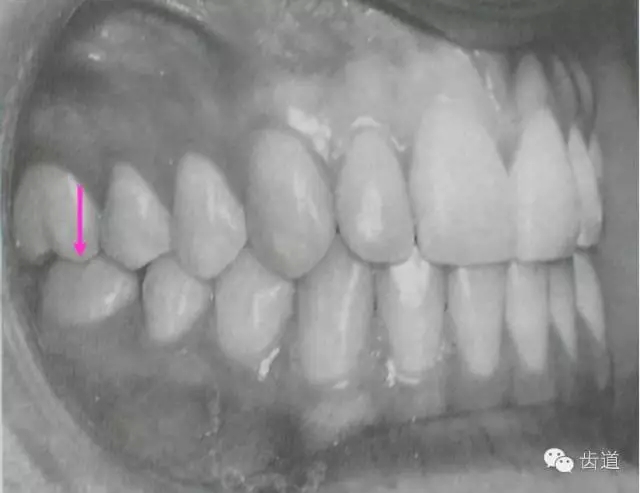

上頜第一磨牙的近中頰尖位于下頜第一磨牙的頰溝近中

典型面形為下頜后縮面形